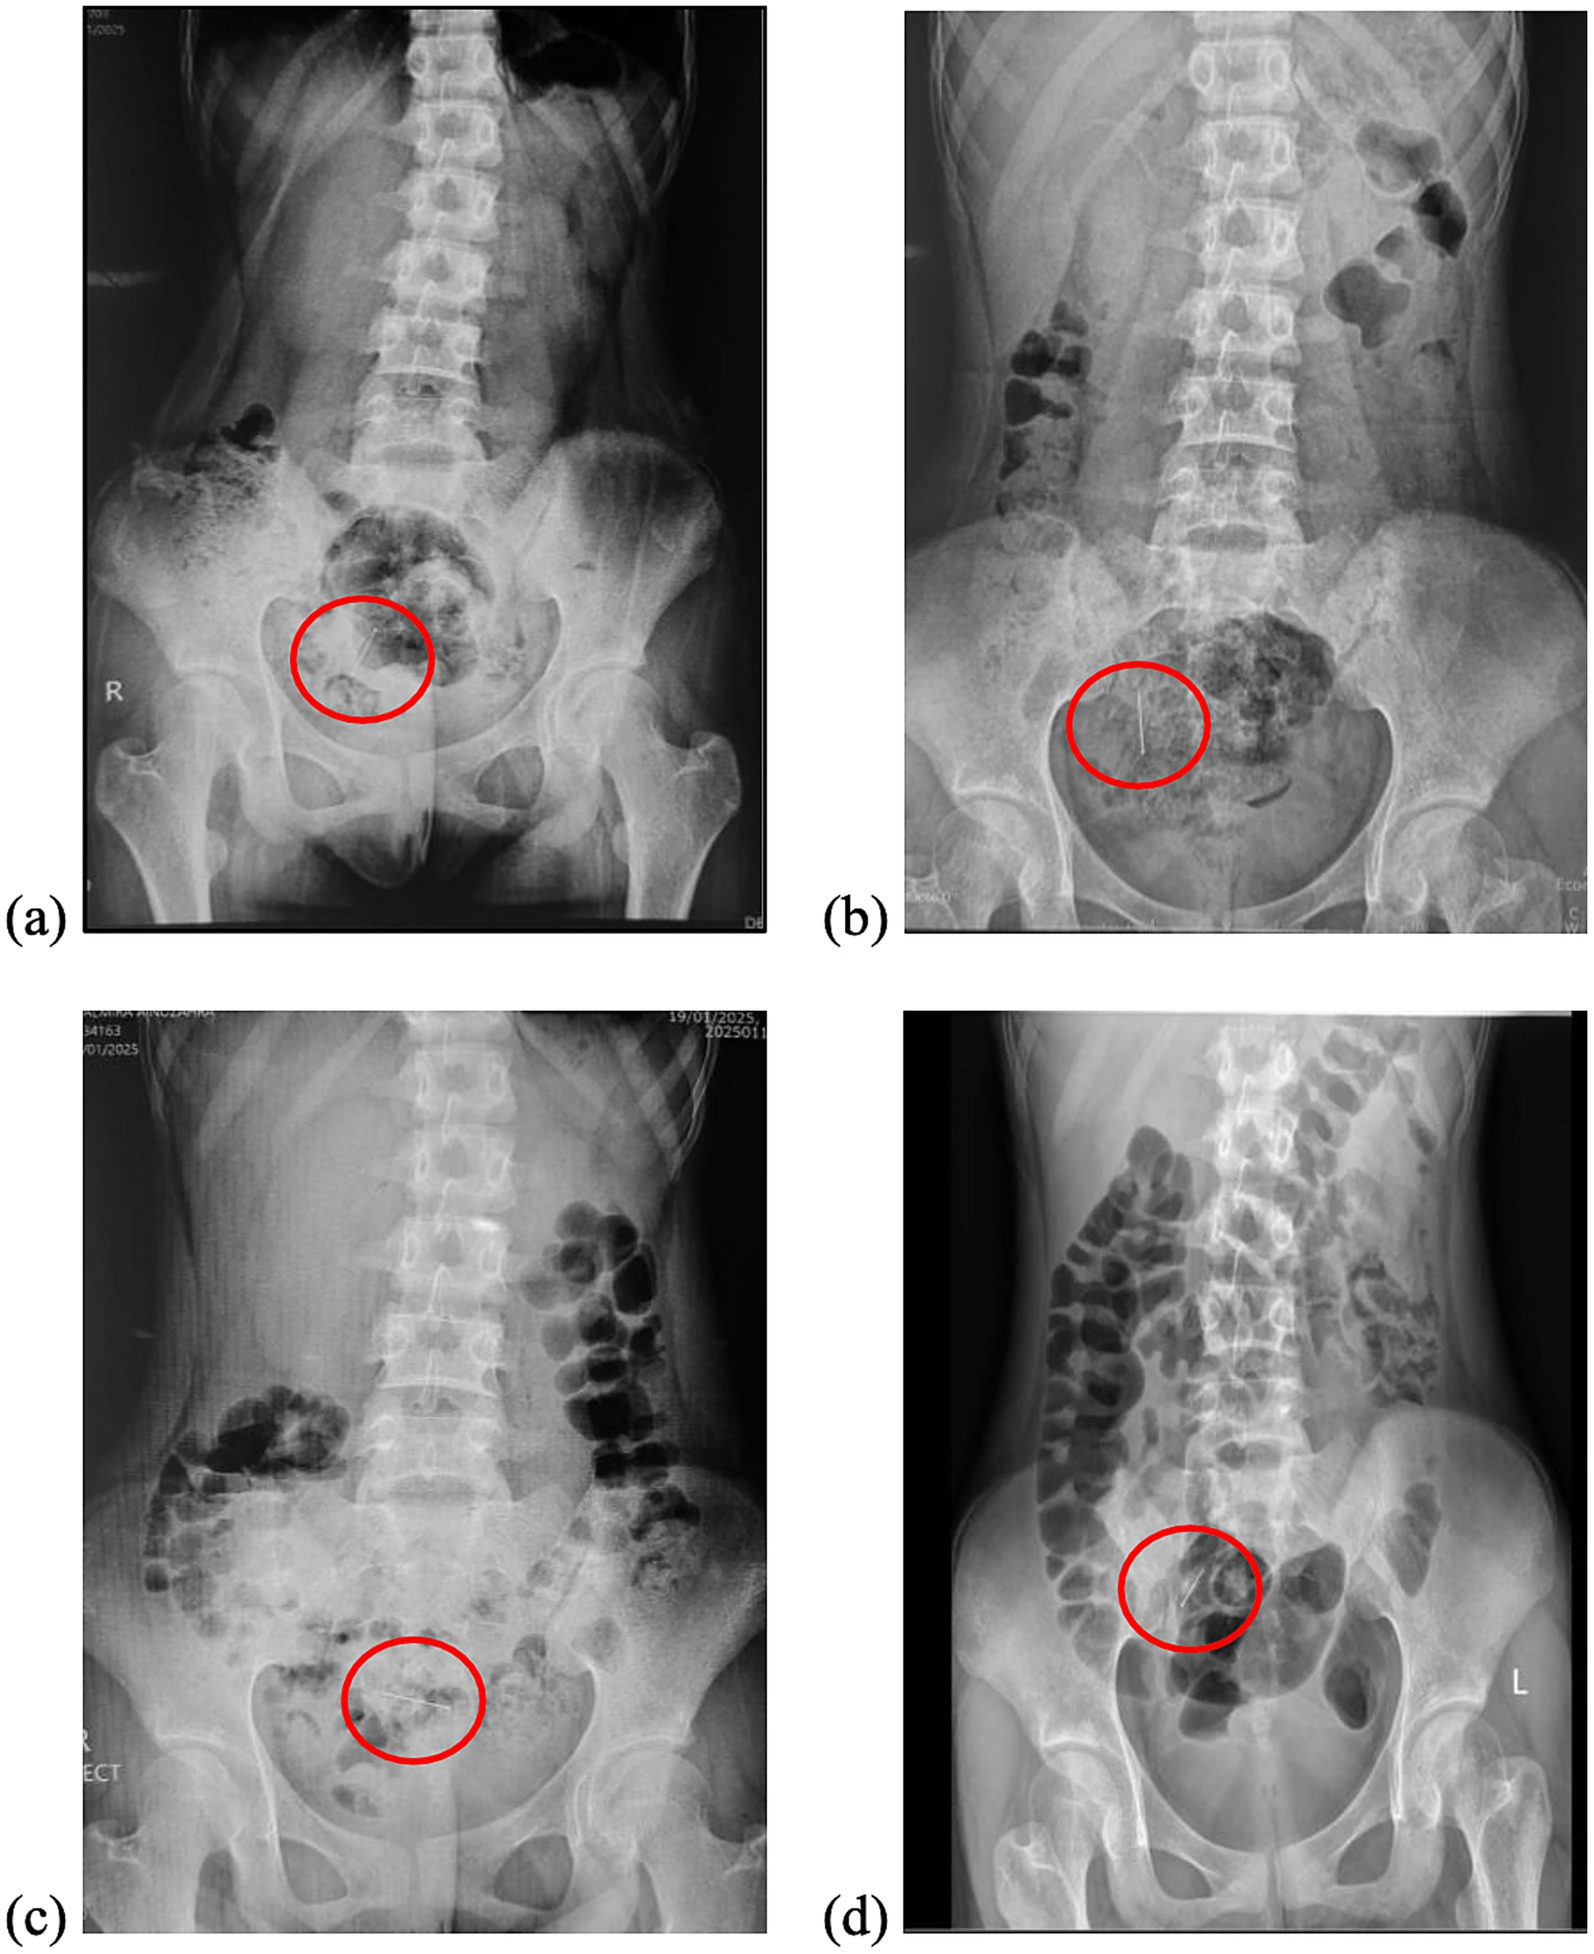

A 16-year-old female presented with a unique case of a three-week history following the accidental ingestion of a headscarf pin, which occurred while she was adjusting her hijab. Initial evaluation at another medical facility involved conservative management that included the administration of laxatives and serial abdominal X-rays. Repeated imaging consistently revealed the presence of a foreign body, persistently situated in the right lower quadrant of the abdomen (Figure 1).

Figure 1. Serial abdominal radiographs demonstrated the presence of a pin (inside the red circle) in the lower quadrant of the abdomen with no acute findings. (a) Day of the ingestion (Day 0), (b) Day 3, (c) Day 7, and (d) Day 21.